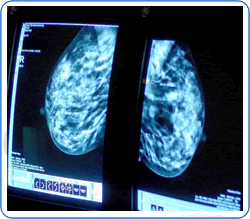

Digital Mammography

Digital mammography is a way of imaging the breast tissue and produces an X-ray called a mammogram. Each breast is compressed between two plastic plates while a beam of X-rays passes through the breast tissue onto an X-ray film.

Two different views of each breast are taken. The process may be slightly uncomfortable but only lasts a few seconds for most women. The mammograms are then immediately reported by the Breast Consultant Radiologist. The radiation dose is very small and does not pose a significant cancer risk.

Occasionally, more detail is required, especially if the breast tissues are dense. In this situation, tomosynthesis mammograms are arranged. This enables the radiologist to look at the breast in ‘slices’ in a similar way to a CT scan.